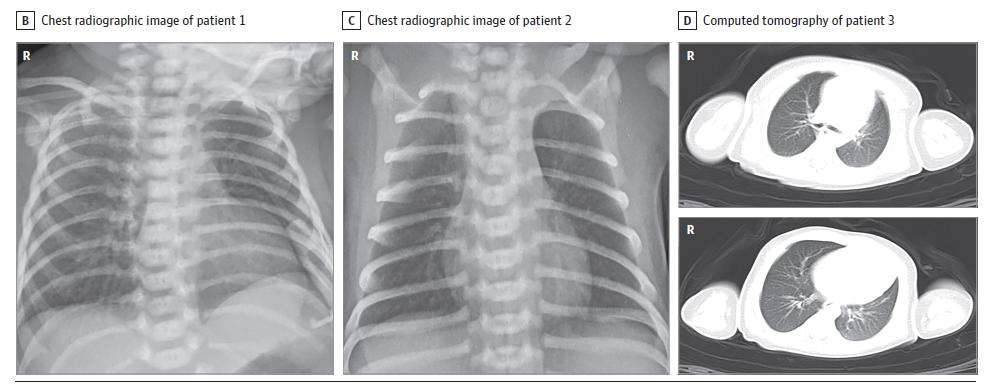

第一位宝宝,他的妈妈40周的时候做了剖宫产,出生后的第二天,小宝宝出现了无精打采和发烧,然后转入ICU,胸片显示有肺炎,其他抽血化验是正常的。

第二位宝宝,母亲40周4天的时候生产,也是剖宫产手术。出生后,宝宝也出现了无精打采、呕吐和发烧。化验显示白细胞增多,淋巴细胞减少,CK-MB升高。胸片同样显示肺炎。

第三位宝宝,母亲在怀孕31周2天的时候,做了剖宫产,因为胎儿出现宫内窘迫。出生后,新生儿出现了呼吸窘迫综合症,胸部影像学检查同样提示肺炎。这位新生儿接受了无创通气治疗、以及抗生素治疗。

生下一个女婴,体重3120克,新生儿没有任何不舒服,立即转入新生儿ICU,出生2小时后,小宝宝的血液被采集,同样发现新生儿的新冠病毒特异性抗体升高,IgG 140.32AU/mL, IgM 45.83 AU/mL,炎症指标也升高,IL-6为28.26 pg/mL,IL-10为153.60 pg/mL,白细胞也升高,肝功能也出现了异常,但是胸部CT是正常的。